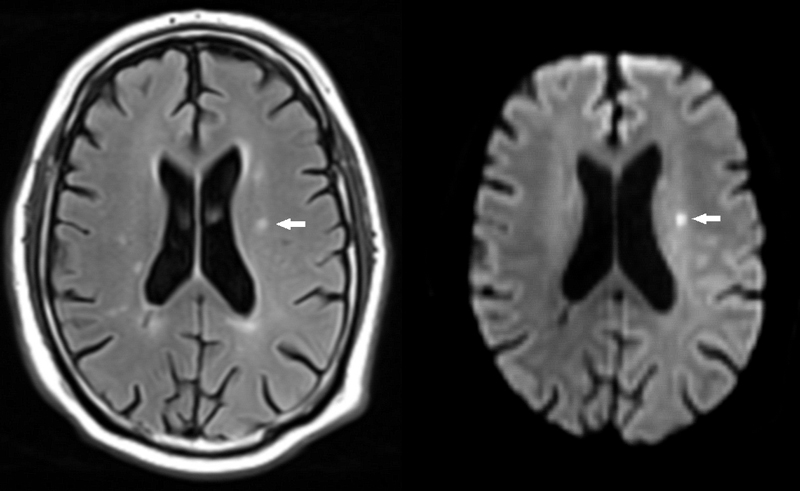

Figure 1 Small ischaemic stroke.

A small subacute ischaemic stroke is depicted on fluid attenuated inversion recovery (FLAIR, left, arrow). The lesion shows signs of restricted diffusion and is hyperintense on diffusion weighted imaging (DWI, right, arrow)